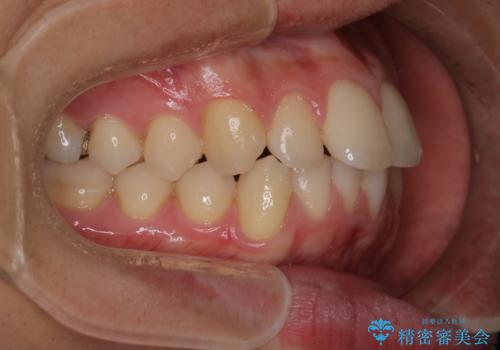

【インビザラインモニター】前歯が出ているのが気になる

- 上の前歯が出ているのが少し気になるとの事で来院されました。

インビザライン希望のため、IPR(歯と歯の間を削る処置)を行うことで、前歯の位置とがたつき整える治療計画を立てました。

患者様よりシュミレーション通りに歯が動くか心配との事だったので

出来るだけ計画通りに歯を動かすために、マウスピース1枚あたりの使用時間を長めに使っていただきました。

そのため、多少治療期間が延びましたが、リファイメント(マウスピースの再発注)なしで終了することができました。